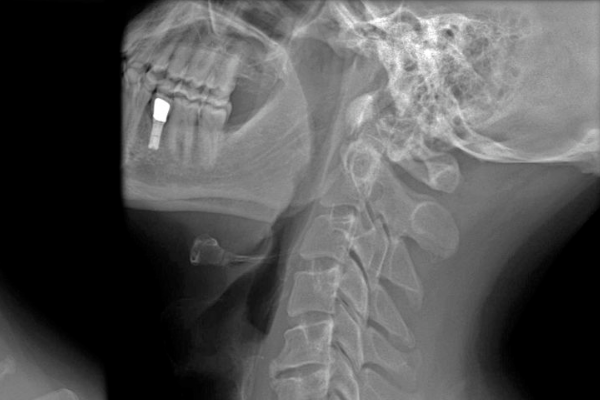

목 디스크란 경추 뼈와 뼈 사이의 추간판(디스크, intervertebral disc)이 탈출하거나 파열돼 경추 신경이 자극 또는 압박을 받아 경항부(목), 경견부(목과 어깨), 견 배부(어깨와 등), 상지(팔)에 통증 및 신경학적 증상을 나타내는 질환입니다. 경추는 운동성이 큰 부위인데요.

경추의 추간판(디스크)은 심각한 압력을 받으면 튀어나와 척수나 신경근을 압박하게 됩니다. 대부분의 목 디스크는 심각한 퇴행성 변화 이후에 일어나기 때문에 많은 환자들이 만성적인 경항통(頸項痛 :목의 통증)에 대한 과거력을 갖고 있는 경우가 대부분입니다. 하지만 편타성 손상(鞭打性損傷 : 교통사고, 낙상, 스포츠 사고로 인한 목 부상)으로 인해 급성으로 발생할 수도 있다고 합니다.